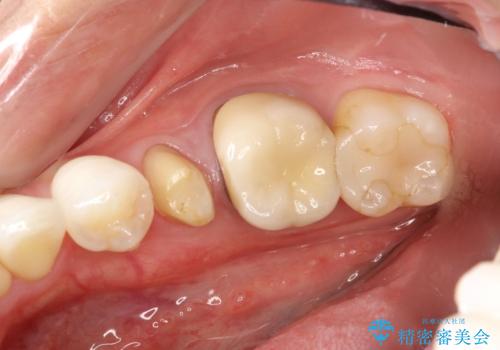

右下5,6間にフィステル(瘻孔)を認めました。デンタルより、右下5根尖に透過像を認め、フィステルに材料を入れてレントゲンにて確認したところ、右下5の根尖に到達しました。

右下5の神経は失活してしまっているため、根管治療の必要性を説明の上、根管治療をした後セラミッククラウンを入れていくこととなりました。

患者さんに確認したところ、今回の右下5は痛みを覚えた記憶はなかったそうです。

神経が死んでしまうときは、多くは痛みを伴うことが多いですが、今回のように気づいたら死んでしまっているというケースもあります。その場合、なかなか自覚症状なく病気が進行してしまうこともあるため、定期的にメンテナンス、レントゲンによる確認をすることが大切です。